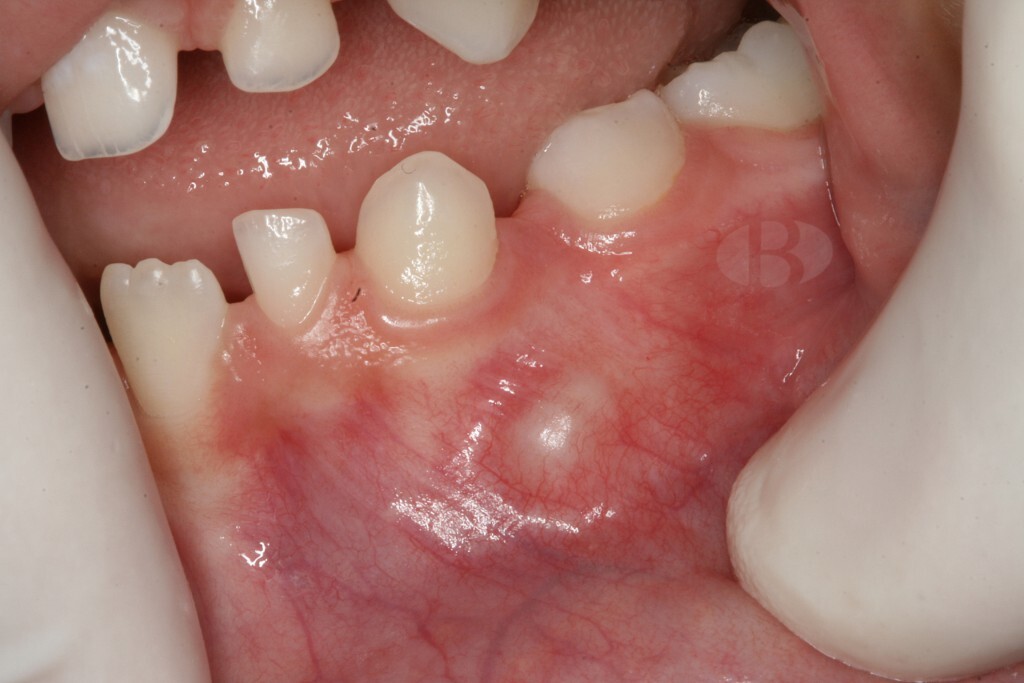

When you hear the word "tumor," there's a good chance you think of cancer. Fortunately, with an odontoma, that's not the case. While an odontoma is a tumor, it's a benign one and not uncommon. That alone is great news! However, odontomas usually require surgical removal. They're made up of dental tissue that resembles abnormal teeth or calcified mass that invade the jaw around your teeth and could affect how your teeth develop. Fortunately, treatment is pretty straightforward and the road to a tumor-free life is one frequently traveled.

Since odontomas grow internally around your teeth, an X-ray from your dentist is necessary to identify them, notes the AAPD. The shape will indicate to your dentist whether it's compound or complex. While they are asymptomatic, the West Indian Medical Journal Review notes your odontoma could cause:

Nearly 80% of those affected by odontomas, though, have teeth that haven't erupted yet. Plus, since they're noncancerous, they rarely grow back after removal.